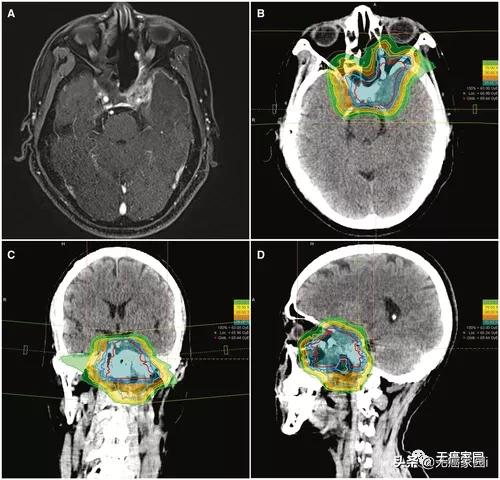

典型的碳离子放射治疗 (CIRT) 治疗计划,包含 3 个视野。该患者患有局部晚期、局部复发性鼻咽癌(T4N0M0 疾病),接受了63gray的碳离子放射治疗,分 21 次。